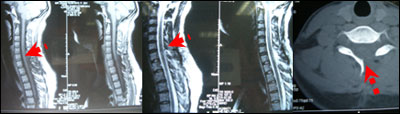

术后疼痛缓解,无其他不适,无并发症。术后病理回报为神经鞘瘤。

术后图片: